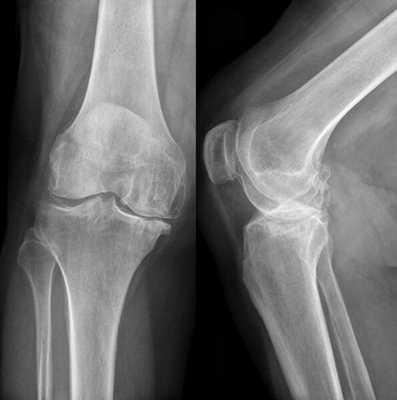

Инструментальные методы диагностики

Самым информативным методом диагностики ПКС является магнитно-резонансная томография (МРТ) коленного сустава. МРТ позволяет визуализировать мягкие ткани в области сустава и поставить окончательный диагноз [2] .

Признаки разрыва ПКС:

- связка не визуализируется;

- нарушена непрерывность её волокон;

- нетипичное расположение волокон;

- косвенные признаки — связка имеет волнистый контур, большеберцовая кость смещена вперёд, задняя крестообразная связка значительно отклонена назад.

В остром периоде обязательно проводится рентгенография. Метод позволяет исключить или выявить сопутствующие повреждения костных структур, которые могут указывать на разрыв ПКС:

- Перелом Сегонда — отрывной перелом межмыщелкового возвышения большеберцовой кости (места прикрепления передней крестообразной связки). Целостность связки при этом не нарушена, однако характерные симптомы её разрыва присутствуют.

- Отрыв связок вместе с фрагментом кости.

- Перелом головки малоберцовой кости.

Для выяснения характера, выраженности и локализации изменений врач современной медицинской клиники назначает дополнительное диагностическое исследование. Оно включает различные методы визуализации структур, к которым относятся:

Рентгенографическая визуализация

- Рентгенография коленного сустава. Не позволяет оценить состояние хрящевой ткани. Назначается для исключения других патологий и выявления сопутствующих изменений костных структур: расширения суставной щели, уплощения суставных поверхностей бедренной и большеберцовой кости на стороне поражения.